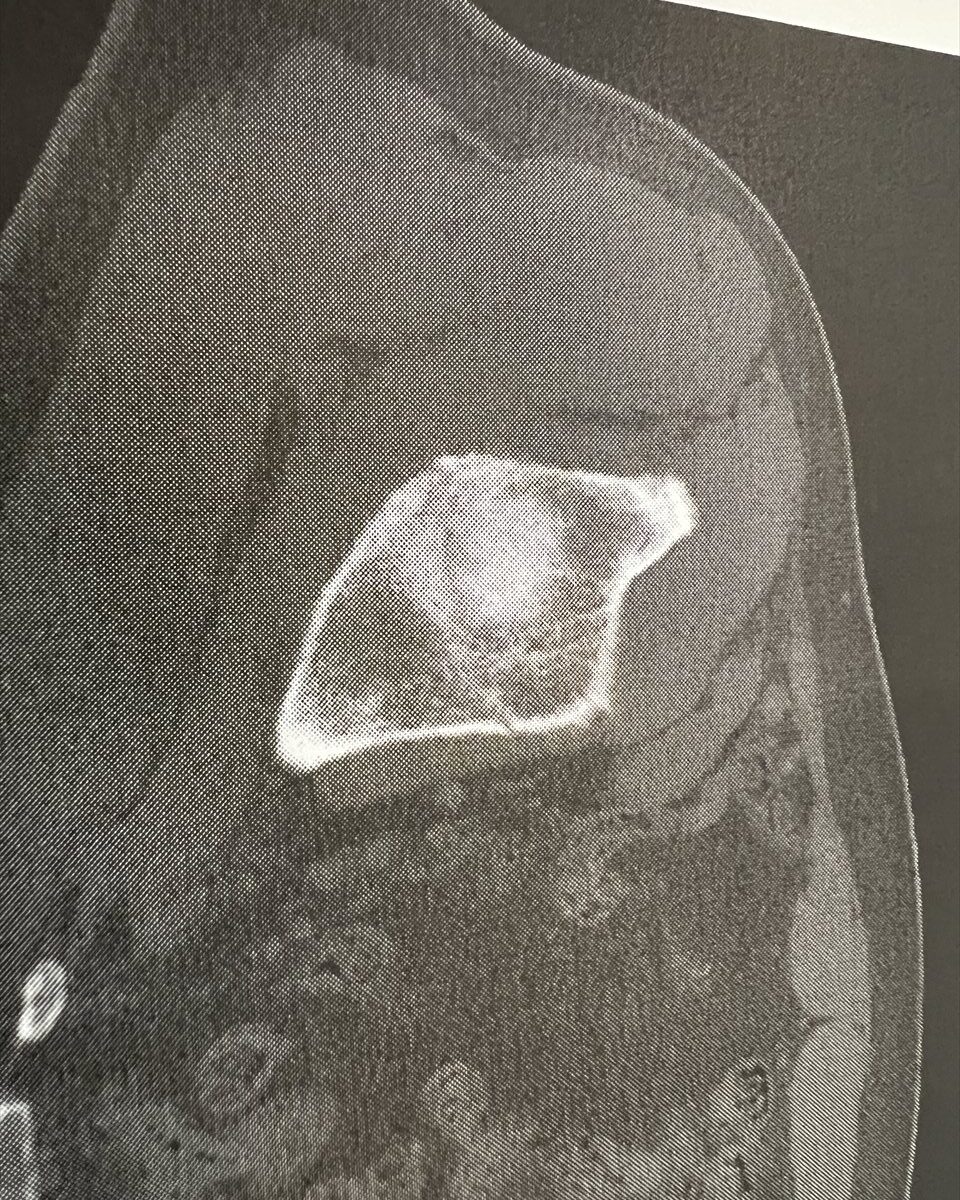

2ヶ月の長きに亘る入院生活も終わりを告げます。骨盤の骨折部分も概ね修復されました。CT写真のとおりです。

最初は、くっきりとスジが見えましたが、だんだんとぼけていき、最終的には、スジが見えなくなってきましたね。

8月9日は、はっきりとエッジのある亀裂が認められるが、10月9日は、完全にぼやけていて、亀裂が不明瞭。すなわち、亀裂がふさがったということですね。